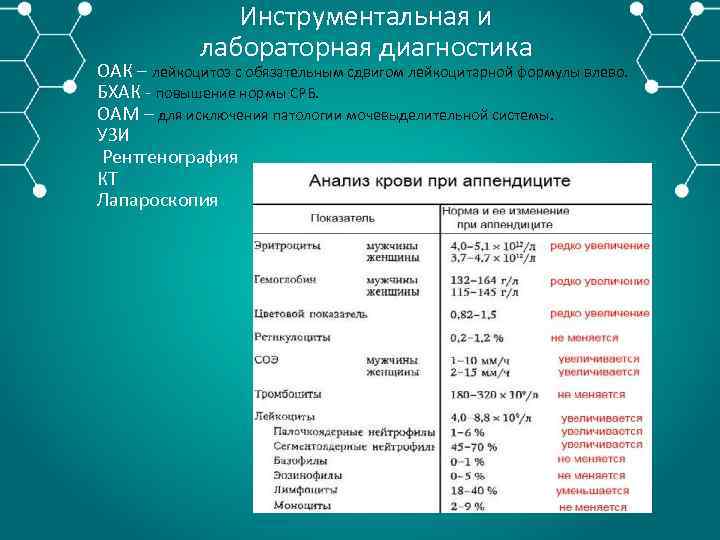

Инструментальная и лабораторная диагностика ОАК – лейкоцитоз с обязательным сдвигом лейкоцитарной формулы влево. БХАК повышение нормы СРБ. ОАМ – для исключения патологии мочевыделительной системы. УЗИ Рентгенография КТ Лапароскопия